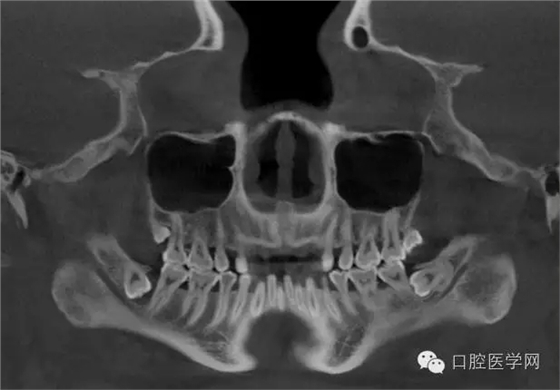

3.牙齒數(shù)目異常

額外牙

X線表現(xiàn):最多見(jiàn)于上頜兩中切牙之間;圓錐形,根短小;拍攝X線片可確定額外牙的數(shù)目、位置、形態(tài)與鄰牙的關(guān)系。

先天缺牙

X線表現(xiàn):常為對(duì)稱性;確定缺牙數(shù)目。